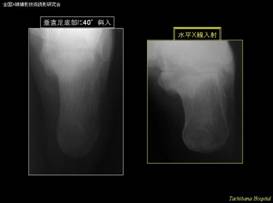

② 患者さんに優しい踵骨軸位水平X線撮影法(踵骨側面撮影後にそのままの体位で)

体位・入射点:踵骨側面撮影の後、そのままの状態から写真のような体位を作る。

撮影距離は100cm以上とし、踵骨―フィルム間に20cm程度のグレーデルテクニックを用いる。撮影条件は管電圧60kVくらいで適切な濃度が得られる照射量とする。

入射点は、内果下端と舟状骨粗面を触知しラインを作り、そのラインに平行で、2cm足底寄りに直交入射する。